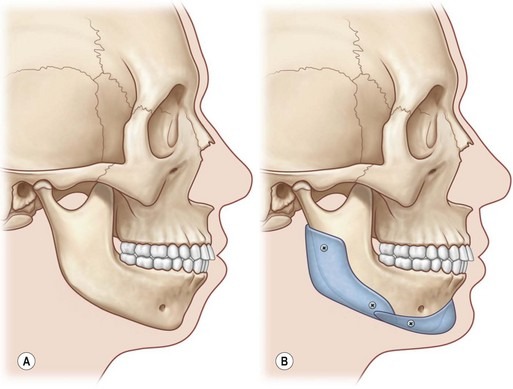

- Mandibular retrognathia: Receded lower jaw

- Surgery: Jaw advancement or reconstruction